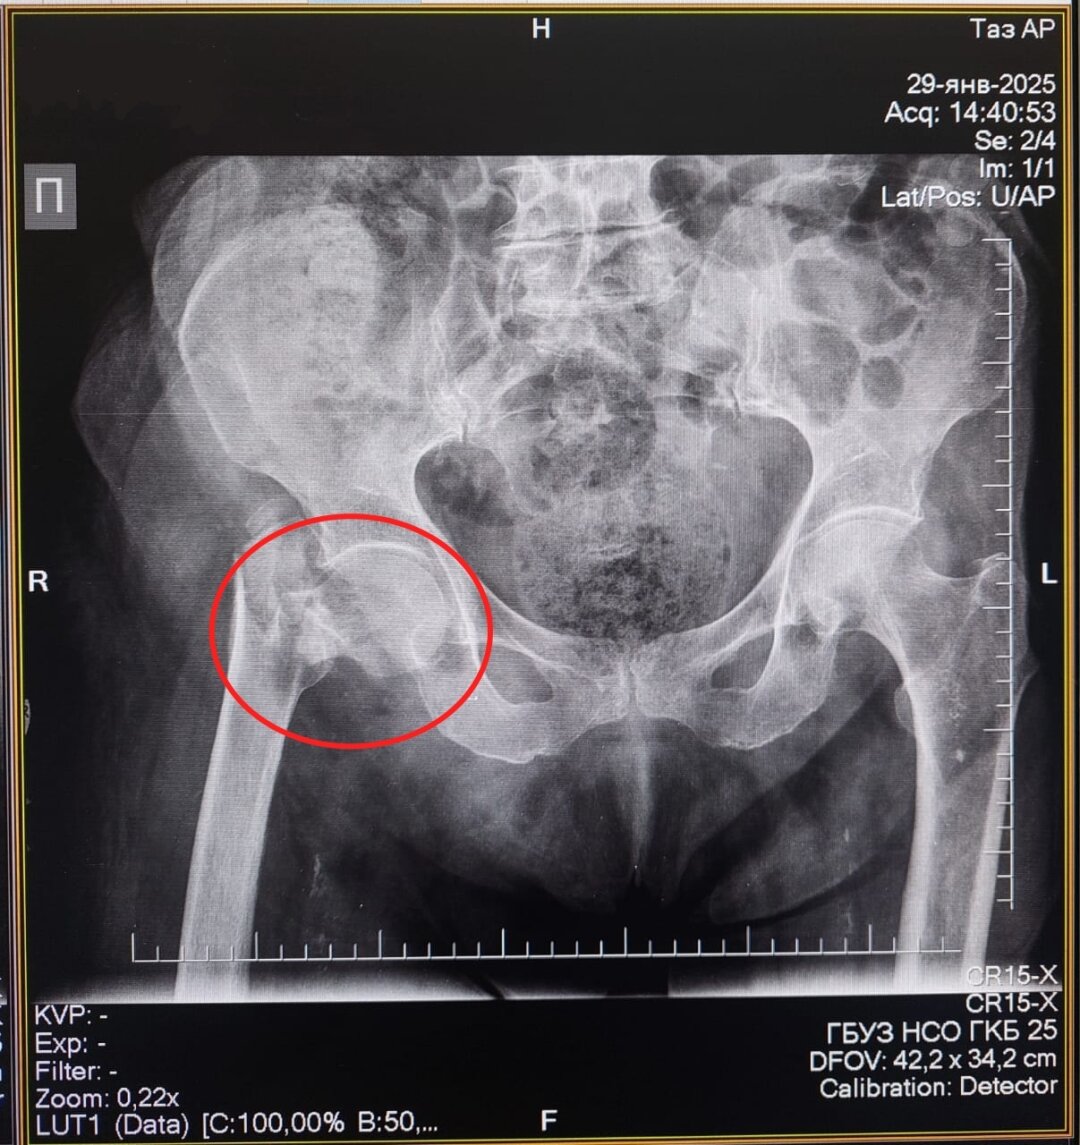

91-летняя жительница Болотнинского района получила перелом проксимального отдела бедренной кости – так эту травму называют врачи – в конце января. Пожилая женщина споткнулась дома о порог и упала.

«В ГКБ № 25 нашей пациентке провели остеосинтез – сопоставили костные отломки и зафиксировали их металлической конструкцией. Сейчас она уже дома, перед выпиской родственники приобрели ходунки. Она уже получает дозированную легкую нагрузку на сустав. В таких операциях даже в 90 лет почему не отказывают? Потому что чем быстрее пациента активизировать, на ноги поставить, тем прогноз благоприятнее», – подчеркивает Абдель Таймусаев.